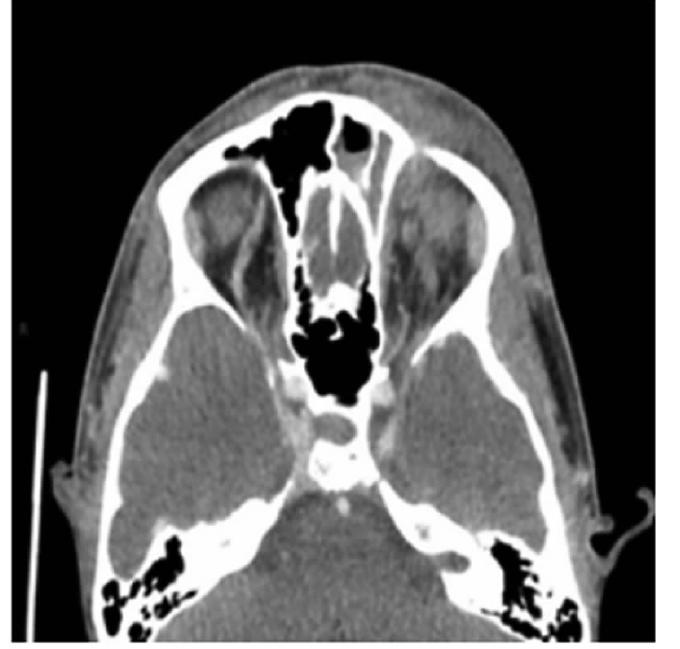

• 神经口腔科学:一个值得关注的新兴交叉学科

2021, 46(7):858-862. DOI: 10.13406/j.cnki.cyxb.002871

摘要 (177) HTML (500) PDF 1.55 M (213) 评论 (0) 收藏

摘要: